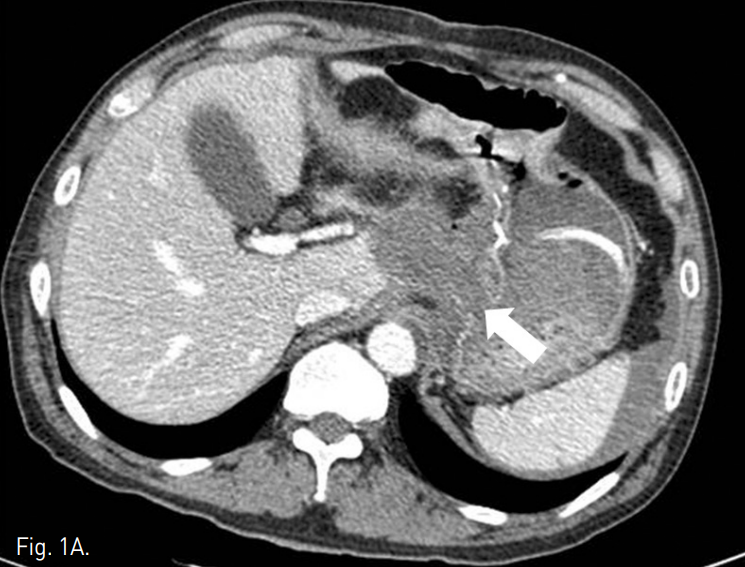

조영증강 복부 CT에서 잔류위의 점막부 조영증강이 일부 끊어져 있는 소견이 보였고, 그 주변으로 혈종과 액체저류 소견이 보여 잔류위 봉합부의 열개(dehiscence)가 있는 것으로 생각된다(Fig. 1a). 액체저류는 주변으로 파급되어 췌장을 둘러싸고 퍼지는 양상이며 비장동맥 주위까지 침윤되어 있었다. 비장동맥의 근위부가 약간 불규칙하게 보였으나 급성 출혈이나 가성동맥류 소견은 뚜렷하지 않았다(Fig. 1b).

Fig. 1

A. Contrast-enhanced CT scan shows focal dehiscence in the residual stomach wall (arrow) with surrounding fluid collection.

B. Proximal splenic artery shows focal luminal irregulari ty (arrow). But there was no evidence of arterial bleding.